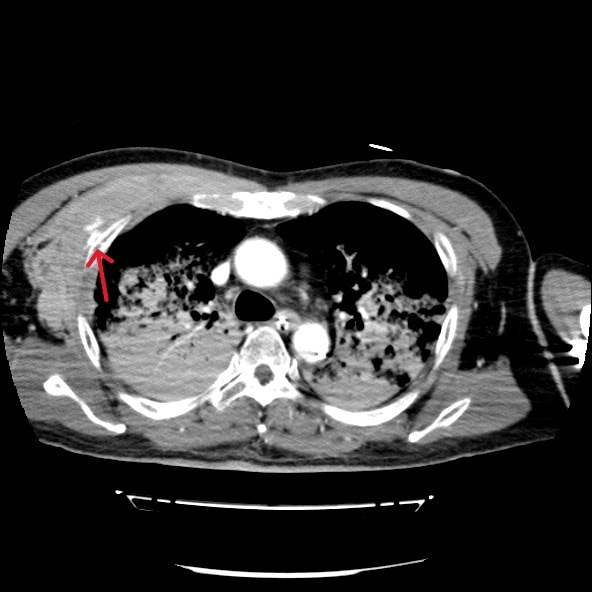

心筋梗塞によって心室細動をきたし心肺停止状態で当院に救急搬送された症例。救命活動が行われ心肺蘇生することができた。その後の経皮的冠動脈インターベンション(Percutaneous Coronary Intervention:PCI)の施行中に経皮的心肺補助法(Percutaneous Cardiopulmonary Support:PCPS)からの脱血不良あり循環血漿量減少が著明に進行していたため、原因精査目的に造影CTを撮影したところ、右第3肋骨周囲の前胸部に血管外漏出(extravasation)が認められた。

胸骨圧迫による動脈損傷が考えられたため、当院放射線科医師により緊急アンギオが施行された。右最上胸動脈および胸肩峰動脈からの出血が確認され、動脈塞栓術(TAE)にて止血することができた。

胸骨圧迫は心肺蘇生において不可欠な救命処置であるが、強い外力により外傷性合併症のリスクが存在する。代表的な合併症としては肋骨骨折や胸骨骨折の頻度が最も高く報告されており、血胸や胸壁血腫などの出血性合併症は報告により約10%程度とされている。ただし、出血源については明確ではなく、動脈損傷に関する症例報告は非常に稀である。特に内胸動脈や肋間動脈、最上胸動脈などの小血管損傷は画像検査が実施されなければ見逃される可能性が高く、臨床的にも認識されにくい。

本症例は、胸骨圧迫後に右最上胸動脈および胸肩峰動脈からの出血を認めた合併症例である。これまでの文献においても、胸骨圧迫後にこれらの動脈からの出血が明確に確認された症例はほとんど存在せず、本症例はその点で非常に特異性が高い。

本症例においては造影CTが循環不全の原因特定、胸骨圧迫による血管損傷の可視化、出血量評価、他臓器損傷のスクリーニングおよび治療方針の決定に有用であった。本症例のような稀な合併症を見逃さないためにも、胸骨圧迫後の症例では、一般的な骨折だけでなく、稀な血管損傷の可能性も念頭に置き、早期に造影CTによる精査を積極的に行うことが重要である。